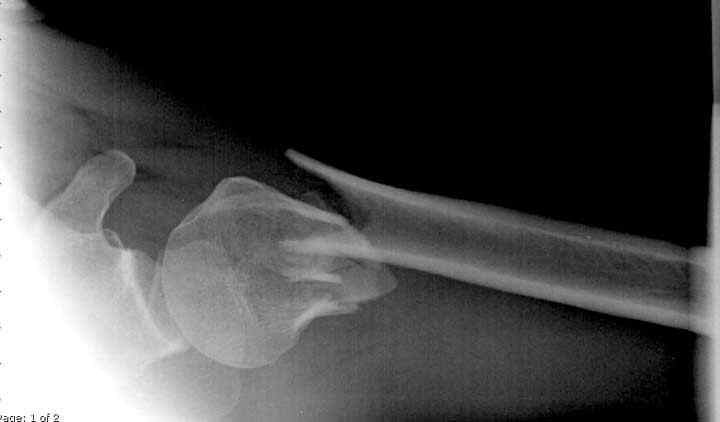

Пациентка Б.1953 г.р., врач-терапевт. Травма 27.11.08г. Падение с высоты роста. Выявлен закрытый не осложненный оскольчатый перелом хирургической шейки левого плеча со смещением. 02.12.08г. оперирована. Выполнена открытая репозиция и остеосинтез пластиной LCP Деост с дополнительной фиксацией отдельно лежащего фрагмента винтом. Послеоперационный период протекал без особенностей, заживление раны первичным натяжением. Швы сняты через 10 дней. Иммобилизация левой верхней конечности клиновидной подушкой 4 недели. По окончании срока – рентген-контроль и умеренная разработка плечевого сустава. В течении месяца функция левого плечевого сустава восстановилась удовлетворительно: поднятие руки до 110 гр., отведение - 90 гр. и до 110 гр. отведение с лопаткой. Отведение руки назад – 20 гр. Наружная и внутренняя ротация – 20 гр. Пациентка по настоянию самостоятельно вышла на работу. 27.03.09 при контрольном осмотре жалоб не предъявляет, болевой синдром в левом плечевом суставе отсутствует. Отведение плеча активно до 90 гр, пассивно с лопаткой до 110 гр., поднятие – 110 гр, отведение назад 20 гр, наружная и внутренняя ротация по 20 гр. На контрольных рентгенограммах отмечается смещение металлоконструкции, ротация головки плеча с приведением дистального отломка на 13 гр. и смещением к зади на 30 гр. Рентгенограммы прилагаются. Ваш взгляд на дальнейшую тактику лечения пациентки?

Уважаемый Евгений, похоже, что первый и второй Р-снимки выполнены несколько в разных положениях(ротация) плечевой кости, в связи с этим создается впечатление смещения пластины. Остеосинтез выполнен при угловом смещении отломков.Таковым и остался. Данная ситуация была бы очевидна гораздо раньше, если бы при контрольной Р-графии были выполнены снимки в 2-х проекциях.(Не в обиду, сам иногда выполняю только один).

Здесь пример открытой репозиции 57 летнего с переломом плеча (1,2) смещение обнаружено на интероперационном снимке. При нормальной прямой проекция (3) угловое смещение обнаружили в аксиальной проекции (4)